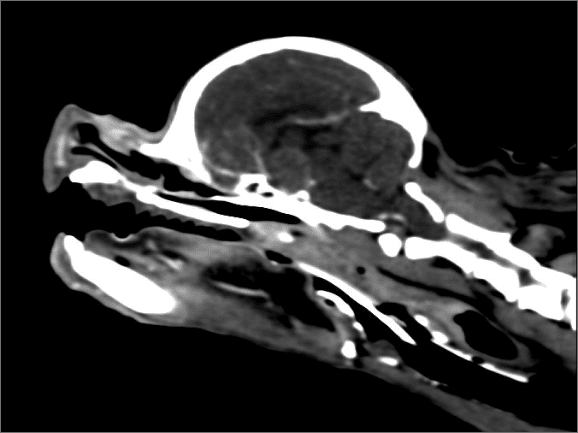

부신에서 코르티솔이 과다하게 분비되어 발생하는 질환.

뇌하수체 종양에 의해 부신이 자극받는 경우가 가장 흔함.